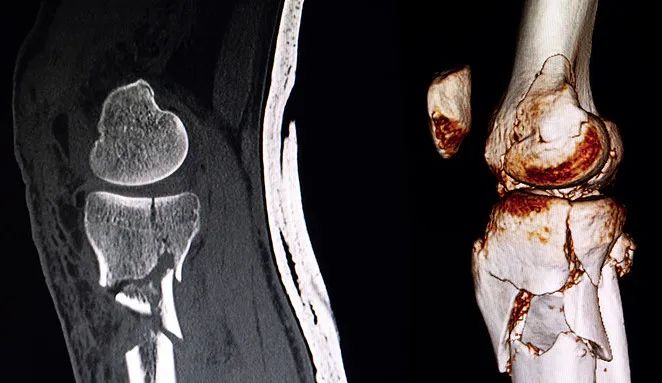

6.Ⅵ型 約占20.8%

雙側(cè)平臺(tái)骨折加脛骨干與干骺端分離,常合并膝部軟組織嚴(yán)重?fù)p傷、筋膜室綜合征和嚴(yán)重神經(jīng)血管損傷。

解決方案:

切開(kāi)復(fù)位,脛骨平臺(tái)解剖鋼板或T形鋼板固定。